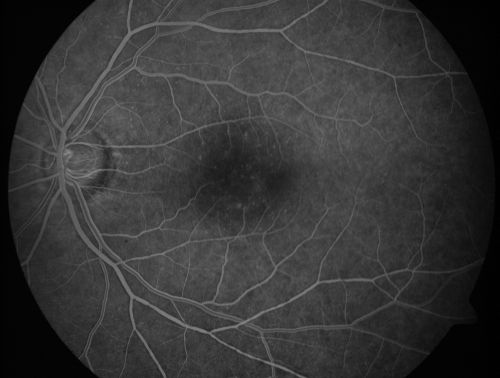

Juxtafoveal Telangiectasis - After Hemorrhage Absorbed Right Eye with Avastin Injections

73-year-old woman has juxtafoveal retinal telangiectasis in both eyes.  The right eye has stage 5 disease.  Her last Avastin treatment in the right eye was in 6 months ago.  The right eye has been the worst of her two eyes for years.

VISUAL ACUITY: Vision OD is 20/200, OS is 20/50.